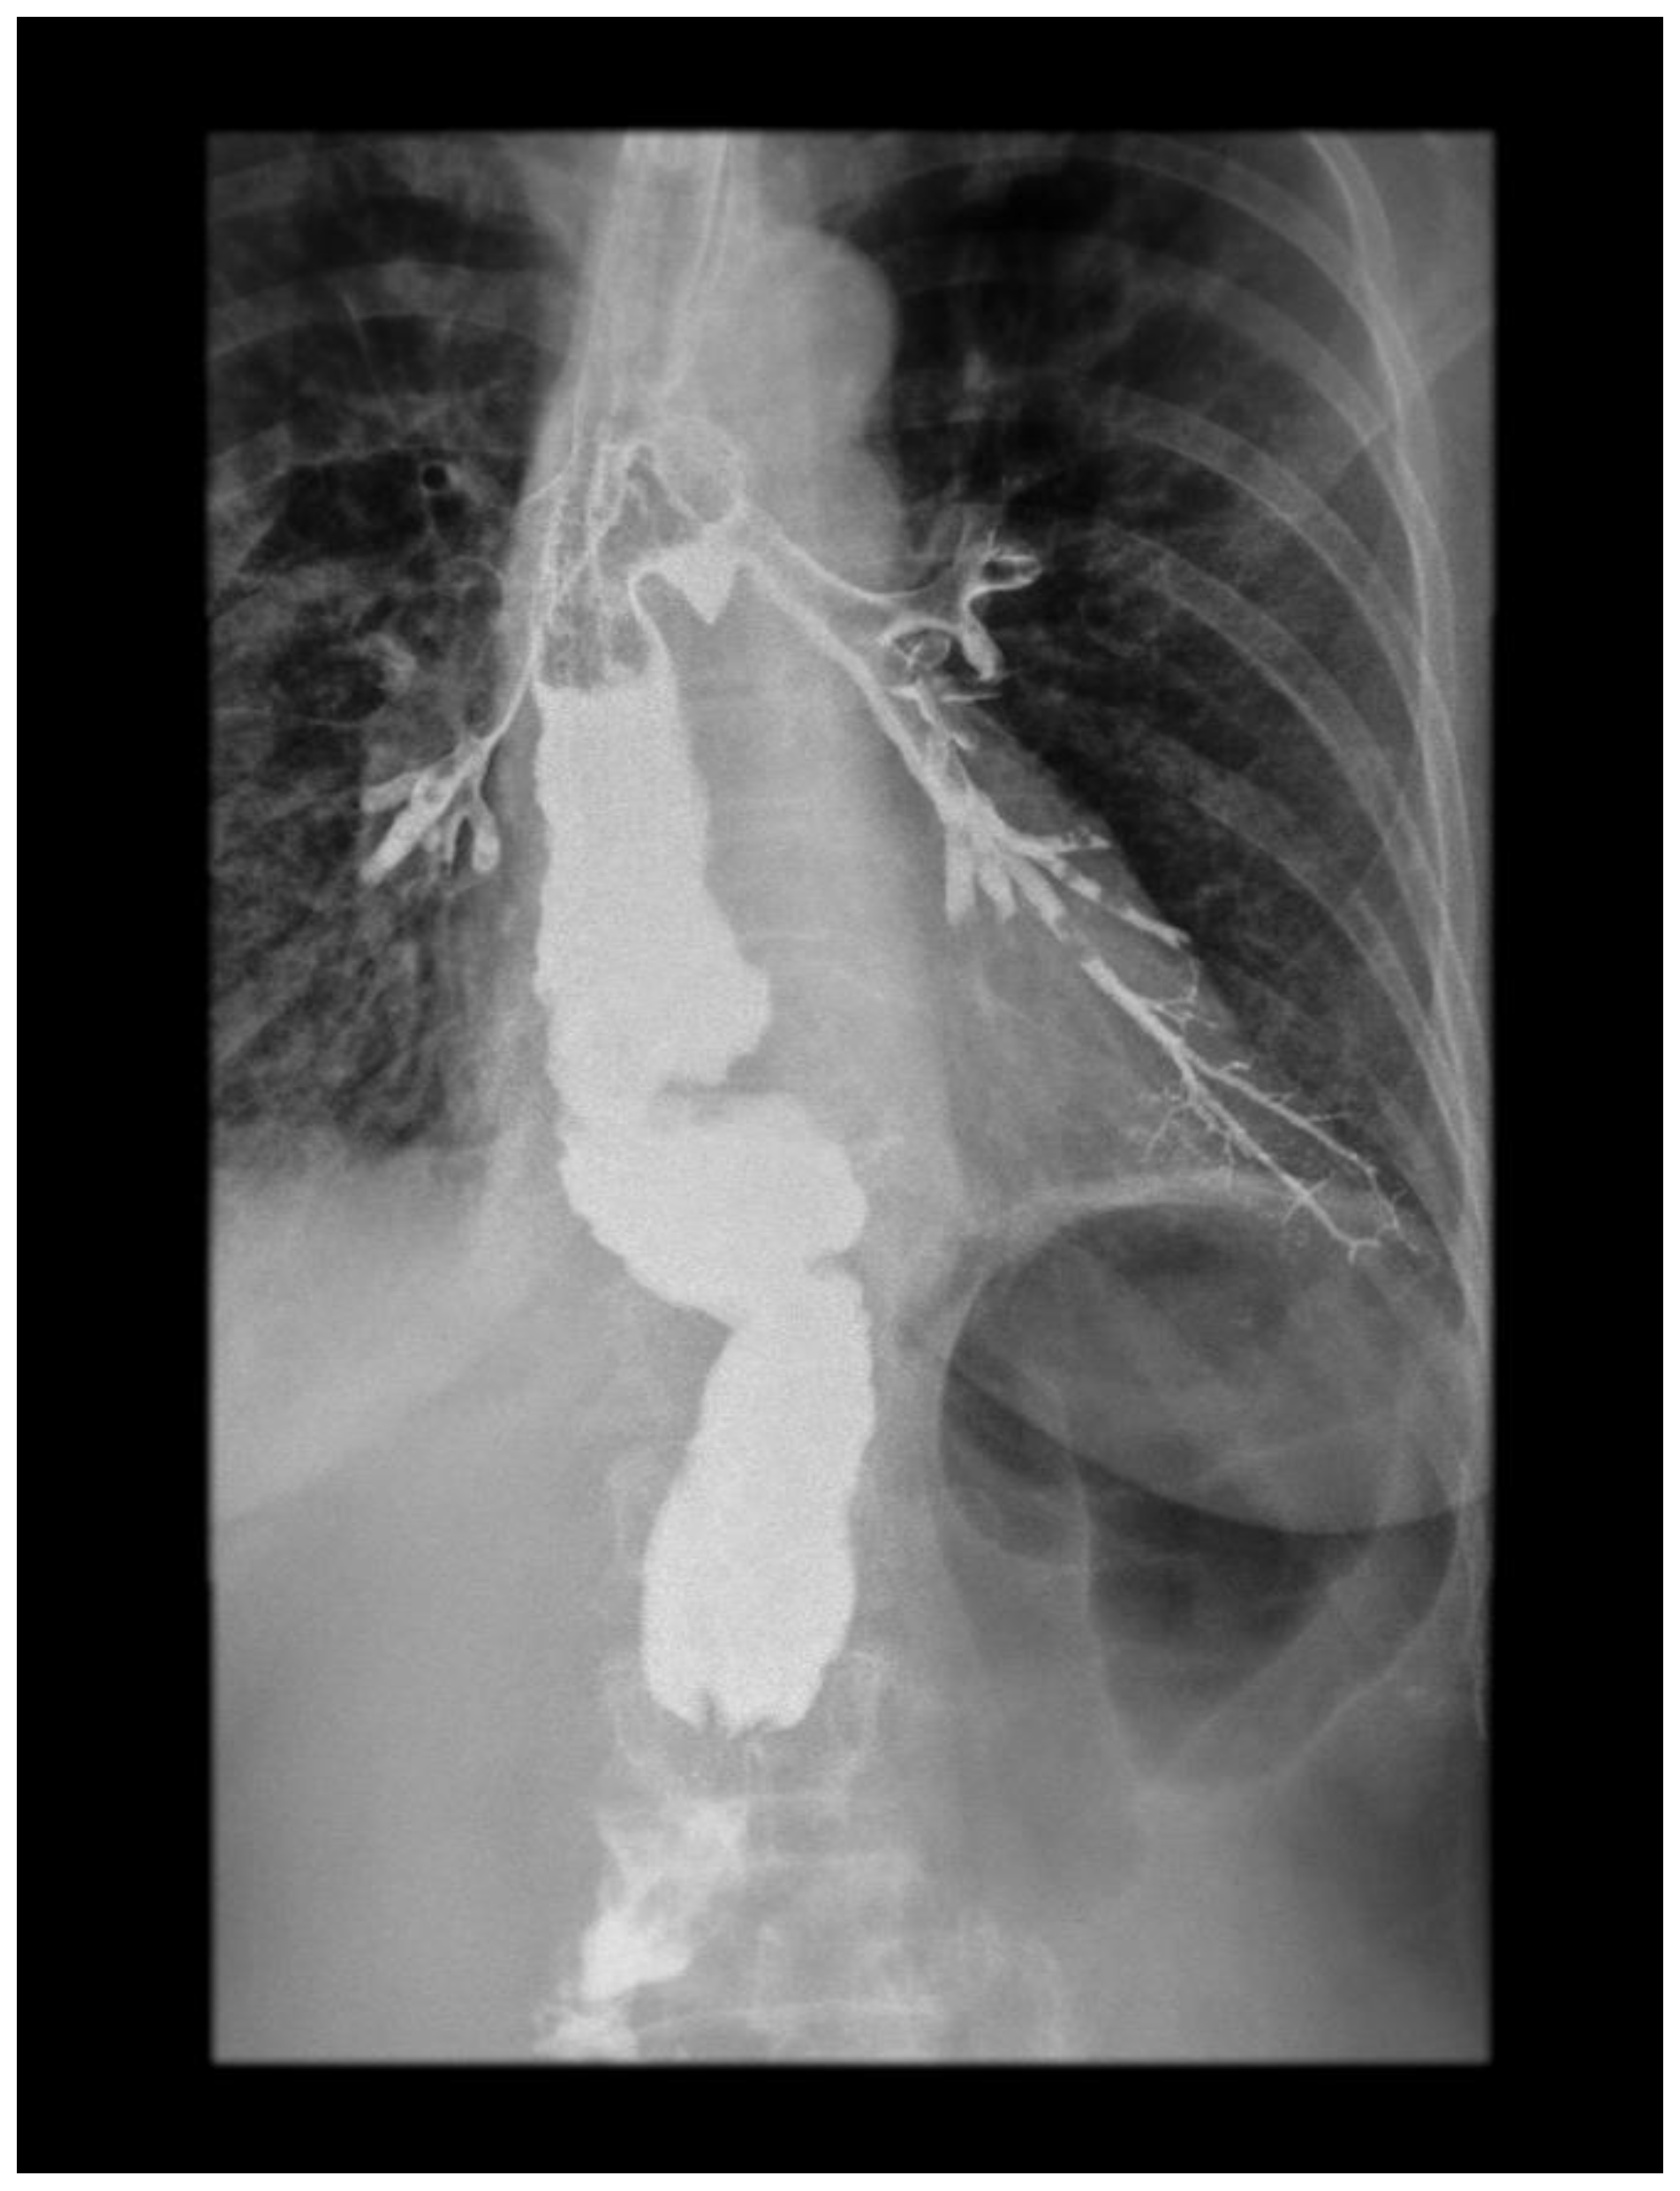

Then, 45 days after surgery, the patient was admitted to a regional hospital due to severe dyspnea, coughing, and vomiting, as well as clinical signs of pneumonia. Laboratory findings showed elevated levels of C-reactive protein (CRP) and white blood cell count (WBC). She was then transferred to our department for further evaluation. Upper gastrointestinal (GI) endoscopy was performed, showing a fistula opening to the airway at the level of the esophagogastric anastomosis (Figure 1). At this point, the presence of a tracheobronchial fistula (TBF) was suspected. A chest X-ray of the thorax showed signs of pneumonia.

Figure 1.

Upper GI endoscopy revealing a fistula orifice (red arrow) at the level of the esophagogastric anastomosis. A gastric tube was placed below (white arrow). At this point, it was obvious that endoscopic treatment of the fistula was not possible. The presence of fibrin around the fistula was indicative of a previous ulcer at the level of the esophagogastric anastomosis and a possible leak that had been clinically undetected.